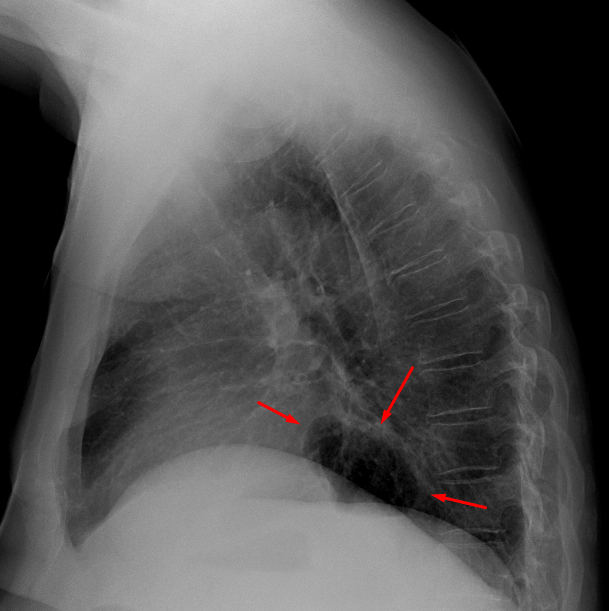

Age: 66

Sex: Male

Indication: Chest pain

Sample ReportStreaky bibasilar opacities likely represent atelectasis. Otherwise, no evidence of acute cardiopulmonary disease.

Moderate sized hiatal hernia.